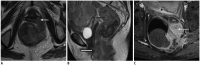

Although a rare disease, anal cancer is increasingly being diagnosed in patients with risk factors, mainly anal infection with the human papilloma virus. Magnetic resonance imaging (MRI) with external phased-array coils is recommended as the imaging modality of choice to grade anal cancers and to evaluate the response assessment after chemoradiotherapy, with a high contrast and good anatomic resolution of the anal canal. MRI provides a performant evaluation of size, extent and signal characteristics of the anal tumor before and after treatment, as well as lymph node involvement and extension to the adjacent organs. MRI is also particularly helpful in the assessment of complications after treatment, and in the diagnosis for relapse of the diseases.